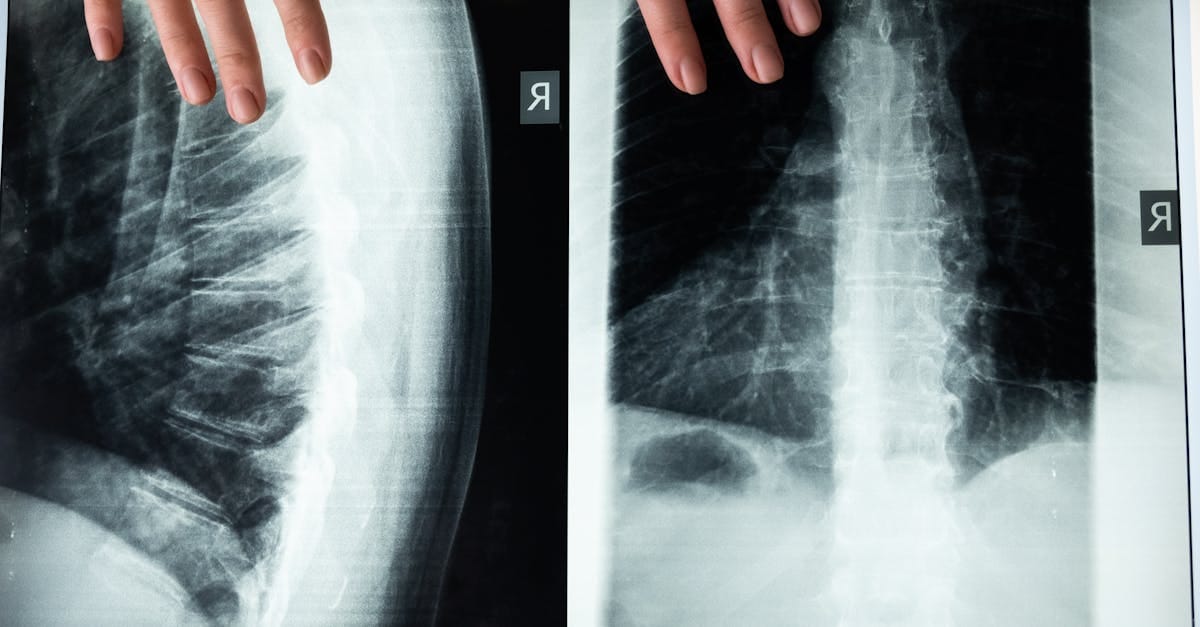

Spinal decompression relies on traction techniques aimed at creating space between the vertebrae. This technique uses automated traction forces to mobilize the joints and relieve tension in the spine. Thanks to specialized equipment, such as the BTL Spinal Decompression, a professional doctor can generate decompressive forces tailored to each patient, thus opening space to promote fluid circulation and the recovery of nerves.

Spinal decompression is particularly indicated for treating herniated discs, spinal stenosis, chronic lower back and cervical pain. These conditions are often caused by compression of the discs or nerves, resulting in sharp and limiting pain. Thanks to the traction theory, patients can benefit from sustained relief and effective rehabilitation without intimidation or pain associated with surgical interventions.